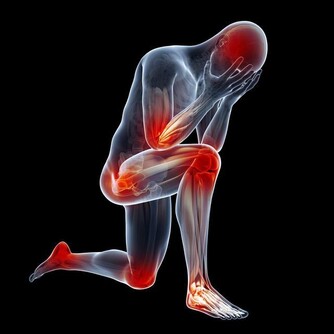

髖關節炎是另一種常見的胯骨疼痛原因,發生率隨著年齡增加而升高。它屬於一種慢性退化性關節疾病,主要表現為髖關節軟骨變薄、磨損,最終導致骨性關節炎。

關節炎發生的關鍵環節是軟骨細胞受到機械性壓力及發炎因子的長期作用,導致軟骨矩陣蛋白降解多於合成,軟骨層逐漸磨薄。

這使得骨頭直接互相摩擦,刺激受壓骨膜出現增生性改變,患者在運動時會感到壓痛不適。

隨著軟骨變薄,關節活動範圍也逐漸限制,嚴重時可完全喪失功能。X光檢查可見關節間隙變窄、骨贅形成。而且病灶還多累及胯骨內側。在治療方面,臨床可採用物理治療、適度運動等保守治療。對於晚期嚴重者可選擇人工關節置換手術。

預防髖關節炎的關鍵在於保護關節。為此要合理控制體重,改善姿勢,不扭動胯部。同時適量運動也有助關節營養和延緩退化。中老年人也應多補充維生素C、鈣質等,延緩軟骨破壞過程。否則最終可能需承受手術風險及復原痛苦。